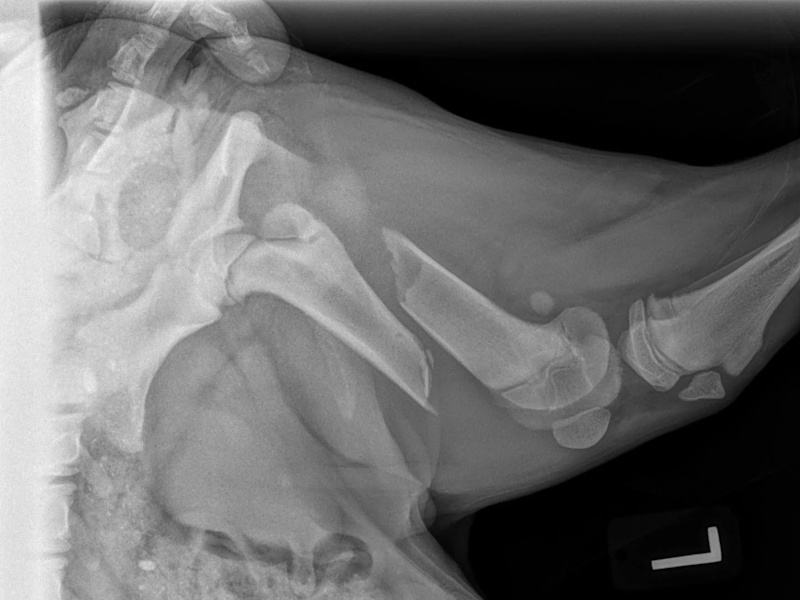

Hip Dysplasia

Hip Dysplasia in canines

Surgical Treatments of Hip Dysplasia

Coxofemoral Luxation (Hip Dislocation)

Hip Dislocation in canines

Treatment Option for Hip Dislocation